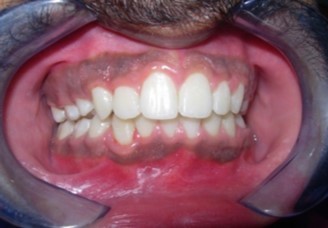

Results

The soft tissue frontal and profile improved dramatically. (Figure 7a-b). The bilateral posterior crossbite was corrected. The severe increase in overjet of about 13mm was effectively reduced to 3mm and the severe deep bite was also corrected (Figure 7c,Figure 7d). Fixed maxillary and mandibular lingual retainers were given. (Figure 7e, Figure 7f). Post orthodontic treatment, normal root inclinations of the teeth and normal alveolar bone levels was observed. (Figure 8).

Figure 7c.Post-treatment intra-oral-Frontal

Figure 7d.Post treatment intra-oral – Right

The end of treatment result showed a good improvement in the transverse, anteroposterior, and vertical dimensions with markedly improved dentofacial esthetics.

A combination therapy of a banded rapid palatal expansion appliance and orthodontic treatment with pre adjusted edgewise appliance therapy was instrumental in the correction of a severe skeletal Class II malocclusion with an orthognathic maxilla and retrognathic mandible. This two-phase therapy resulted in a dramatic improvement of the facial and smile esthetics with good occlusal interdigitation that enhanced the patient’s speech, personality and self-esteem.